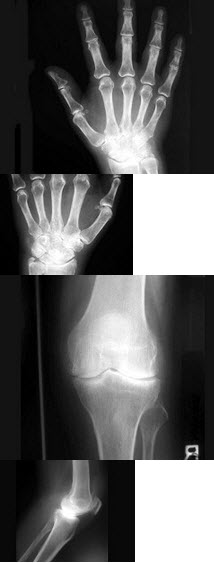

52、单项选择题

女,56岁,手指关节肿胀,疼痛,僵硬,结合图像,最可能的诊断是()

A.关节结核

B.类风湿关节炎

C.痛风性关节炎

D.Reiter综合征

E.骨囊肿

点击查看答案